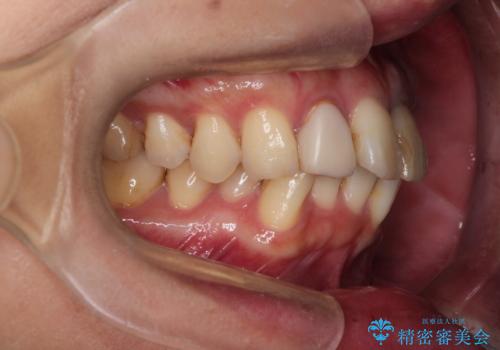

- 全体的なガタガタと前歯をきれいにしたいとのことで来院されました。

下の歯は重度のガタガタがあり、上の前歯は何本かが神経の治療がしてある状態でした。

インビザラインにて歯並びを整え、上顎の前歯にセラミックを装着する計画としました。